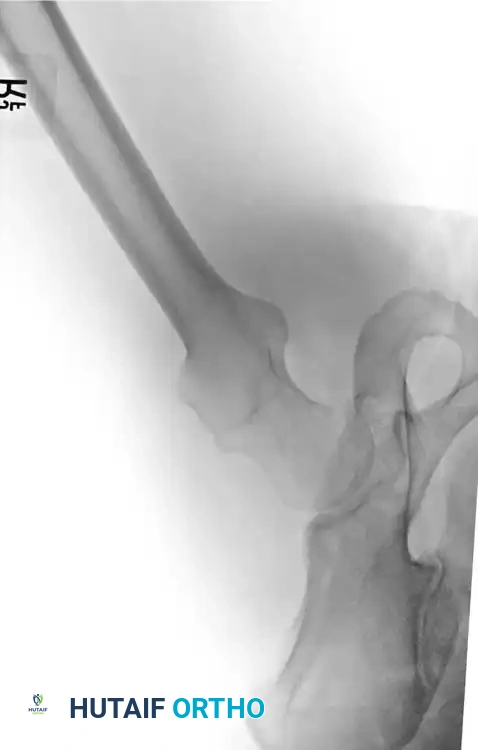

Distal Femoral Osteotomy (DFO)

DFO is indicated for lateral compartment osteoarthritis associated with a valgus deformity. Because the deformity in a valgus knee is typically located in the distal femur rather than the proximal tibia, a medial closing wedge or lateral opening wedge osteotomy of the distal femur is performed.

Surgical Atlas: Osteotomy and Realignment Biomechanics

The following radiographic and illustrative figures detail the preoperative planning, biomechanical axes, and intraoperative fixation strategies critical for successful osteotomies around the knee.

Preoperative templating is mandatory. The mechanical axis must be drawn from the center of the femoral head to the center of the ankle mortise. The degree of correction is calculated to ensure the new weight-bearing line passes through the targeted compartment.

For distal femoral osteotomies, the plate is typically applied to the medial or lateral cortex depending on the wedge orientation. The fixation must be robust enough to withstand the significant bending moments present at the distal femur.